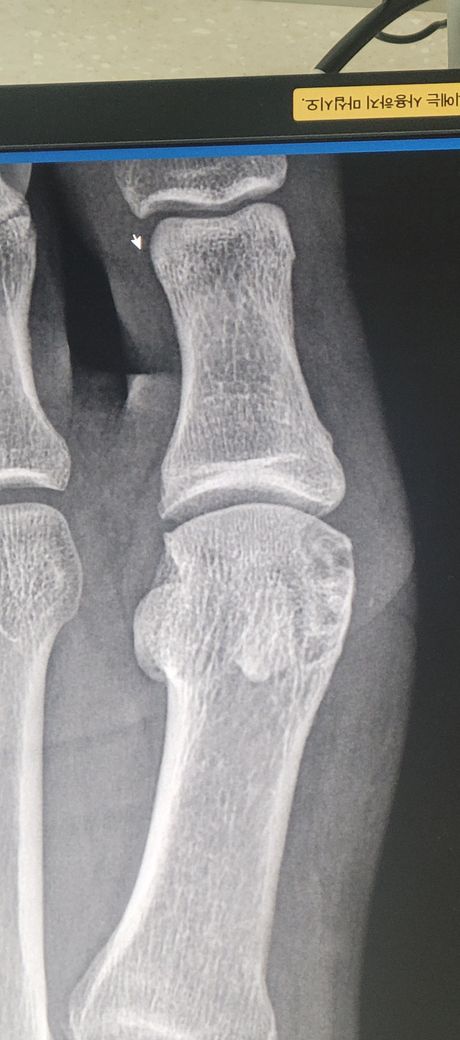

질문자분께서 올려주신 영상자료에서도 특이한 것은 보이지 않는 것 같구요, 다만 요산수치는 성인 남성의 경우 7이하로 유지되는 것이 좋으니 이점은 지속적으로 관리하시는 것을 추천드립니다.